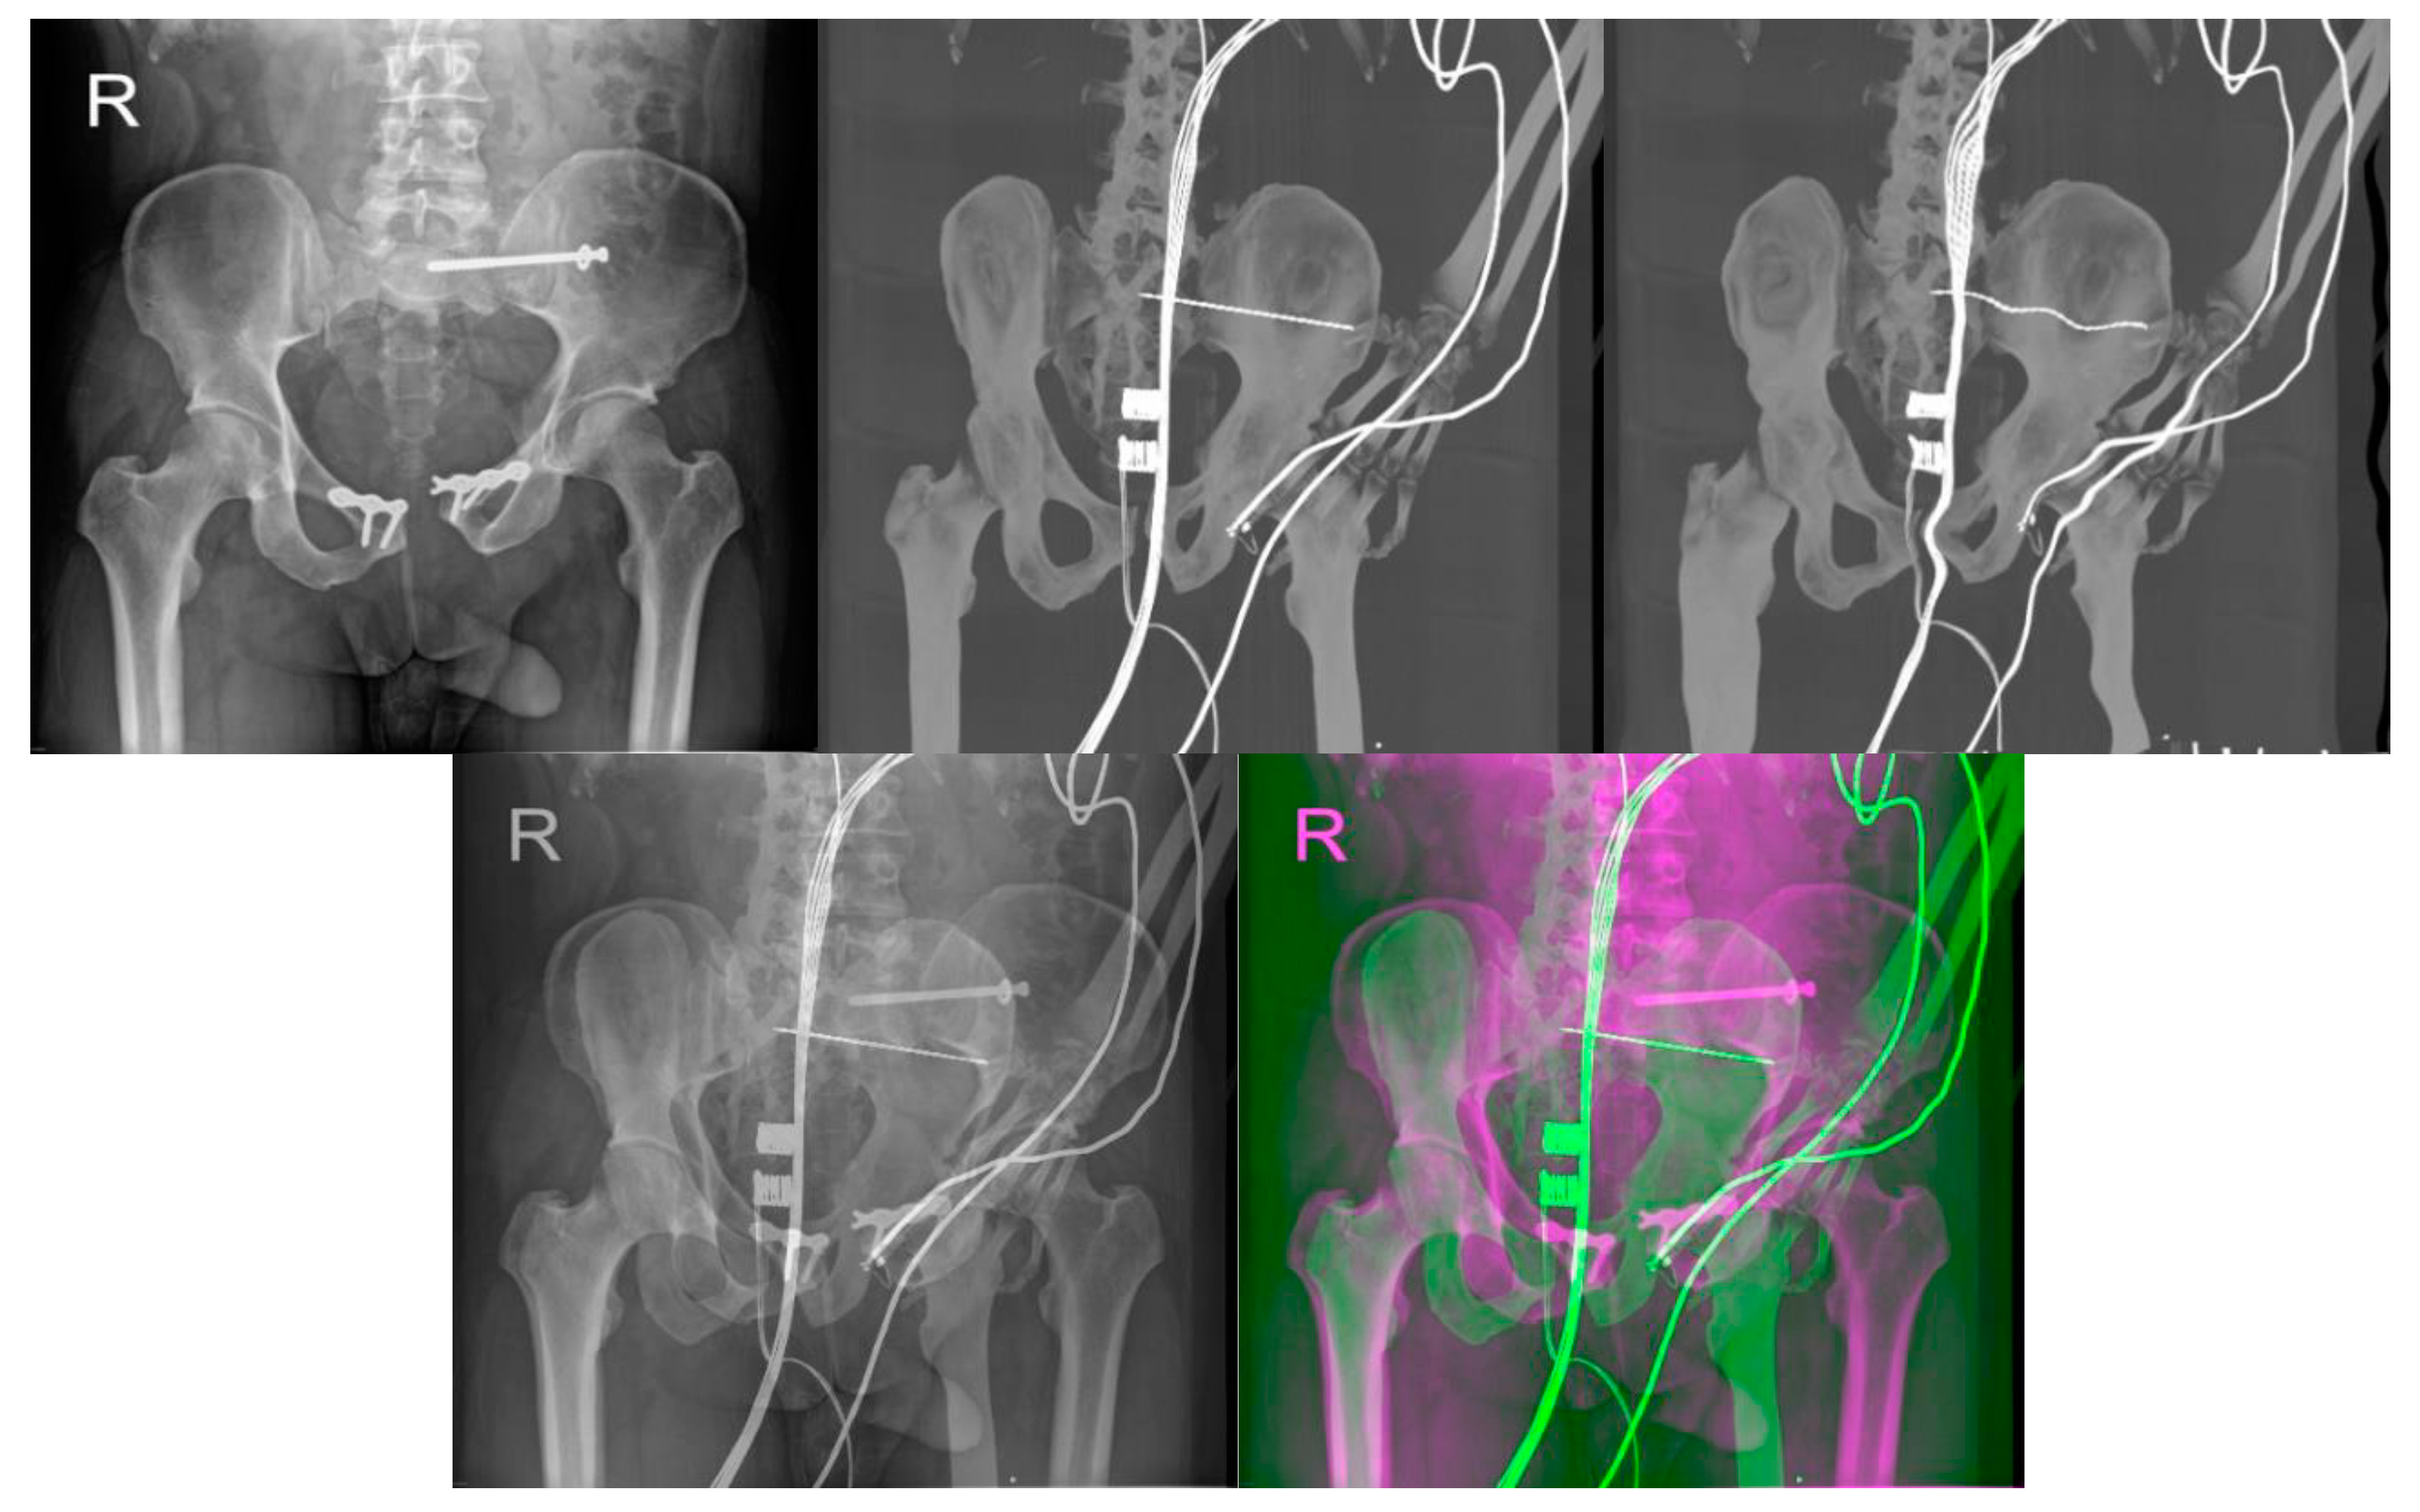

- Reconstructed DDR projections with virtual iliosacral screw

- Multimodal image registration of DRR projections to a reference X-ray image